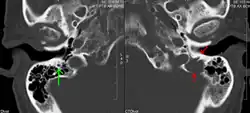

Bone pain affects almost 70% of people with multiple myeloma and is one of the most common symptoms.[2]: 653 [23] Myeloma bone pain usually involves the spine and ribs and worsens with activity. Persistent, localized pain may indicate a pathological bone fracture. Involvement of the vertebrae may lead to spinal cord compression or kyphosis. Myeloma bone disease is due to the overexpression of receptor activator for nuclear factor κ B ligand (RANKL) by bone marrow stroma. RANKL activates osteoclasts, which resorb bone. The resultant bone lesions are lytic (cause breakdown) in nature. They are best seen in plain radiographs, which may show "punched-out" resorptive lesions (including the "raindrop" appearance of the skull on radiography). The breakdown of bone also leads to the release of calcium ions into the blood, leading to hypercalcemia and its associated symptoms.[24]

The diagnostic examination of a person with suspected multiple myeloma typically includes a skeletal survey. This is a series of X-rays of the skull, axial skeleton, and proximal long bones. Myeloma activity sometimes appears as "lytic lesions" (with local disappearance of normal bone due to resorption) or as "punched-out lesions" on the skull X-ray ("raindrop skull"). Lesions may also be sclerotic, which is seen as radiodense.[76] Overall, the radiodensity of myeloma is between −30 and 120 Hounsfield units (HU).[77] Magnetic resonance imaging is more sensitive than simple X-rays in the detection of lytic lesions. An MRI may supersede a skeletal survey, especially when vertebral disease is suspected. Occasionally, a CT scan is performed to measure the size of soft-tissue plasmacytomas. Nuclear Medicine Bone scans are typically not of any additional value in the workup of people with myeloma (no new bone formation; lytic lesions not well visualized on nuclear bone scan).